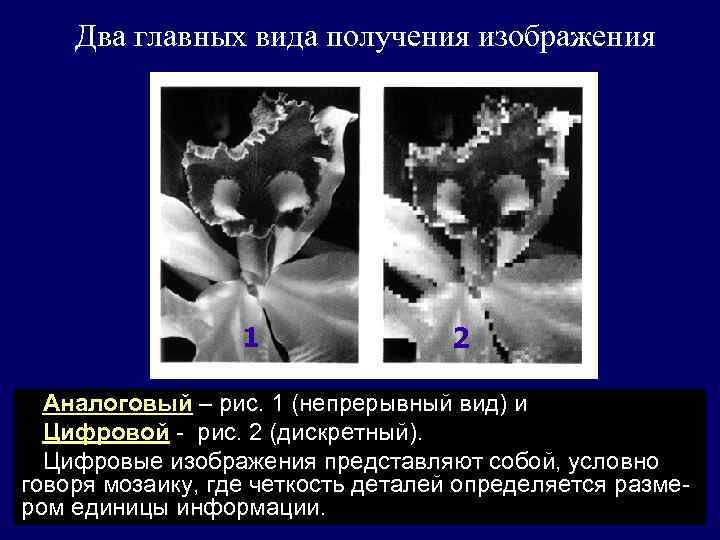

Два главных вида получения изображения 1 2 Аналоговый – рис. 1 (непрерывный вид) и Цифровой - рис. 2 (дискретный). Цифровые изображения представляют собой, условно говоря мозаику, где четкость деталей определяется размером единицы информации.